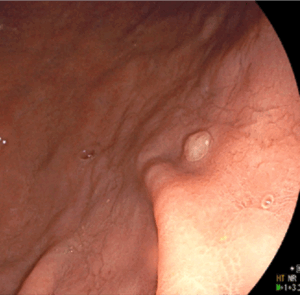

胃カメラであれば経過観察であっても、食道裂孔ヘルニアやバレット食道、胃ポリープと記載されていたり、腹部エコー検査であれば、肝血管腫やら胆嚢ポリープなどなど。

当クリニックのホームページでは、「消化器内科」や「当クリニックで行う検査」などの中に、健診でよく見かける病気について副院長が画像とともに分かりやすく説明をしています。